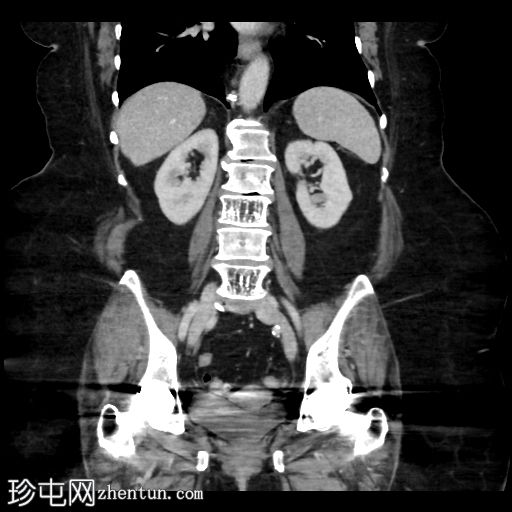

矢状位增强扫描(门静脉期)

可见小食管裂孔疝。胆道积气。胆囊增厚,相对减压,并伴有胆囊十二指肠瘘。空肠至回肠近端中度扩张,回肠近端可见节段性增厚,并延伸至右下腹的移行点。移行点处可见一枚卵圆形层状胆结石,周围有少量吞咽物。双侧全髋关节置换术导致盆腔出现条状伪影。未见其他急性异常。

这是一个典型的胆石性肠梗阻病例,伴有胆囊十二指肠瘘,移行点位于右下腹近端回肠(里格勒三联征)。请注意,肠壁在移行点附近轻度增厚,阻塞性胆结石可能与吞咽物混杂在一起,容易被忽略。此外,还应注意胆囊肠瘘可能被误认为是正常的上消化道解剖结构或十二指肠憩室。这些观察结果有助于强调全面检查的重要性。